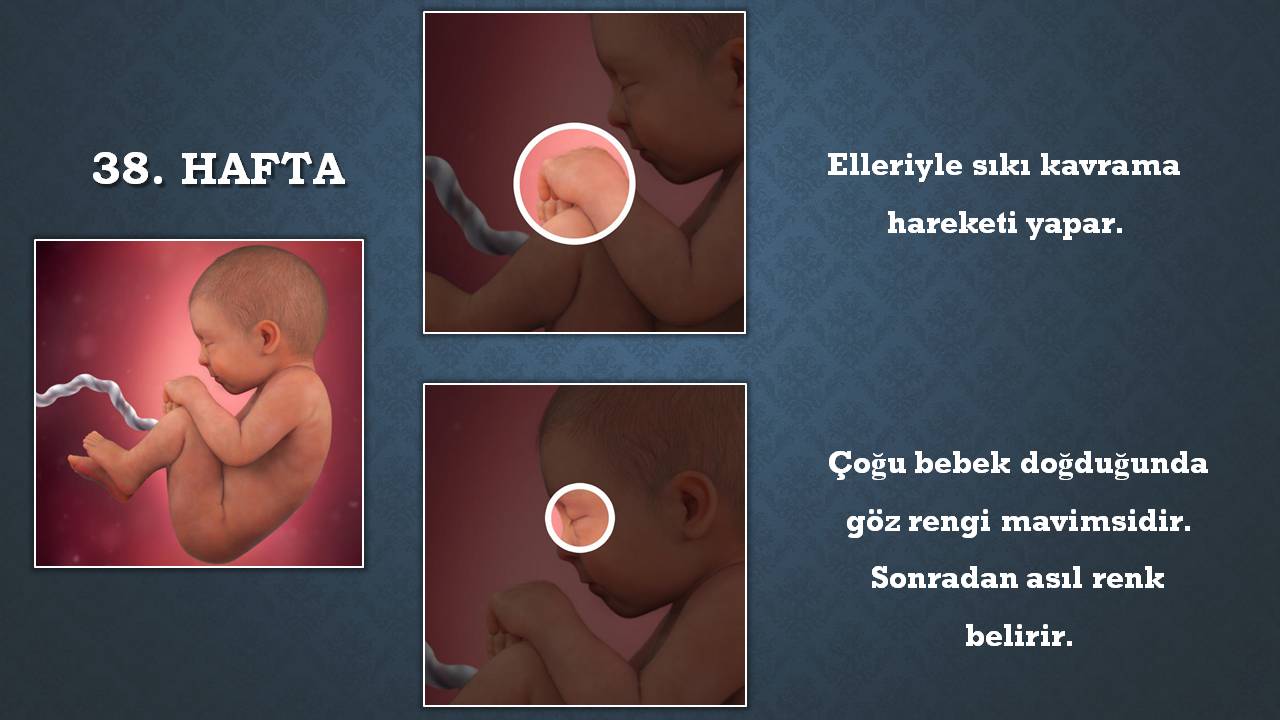

Bebek hareketlerinde azalma neden olur doğum belirtisi mi hamilelikte erkek bebek ne zaman nasıl hareket eder, bebeğim çok hareketli, gebelik bebeğin çok hareketli olması normal mi, bu durum neden kaynaklanır ,38 haftalık gebelikte bebek hareketleri azalır mı? Bebeğiniz ultrasonografide c şeklinde görünmektedir. 8 haftalık gebe olan anne adayı belin çevresinde çok hafif bir değişiklik.